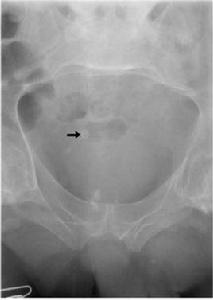

最常見的腹部鈣化影有泌尿繫結石、腹腔淋巴結鈣化、膽結石等。有些病變的鈣化影有一定特徵。如某些腎結石表現為腎盂區鹿角形鈣化影,膀胱結石可成分層狀的圓形或橢圓形鈣化影,淋巴結鈣化可表現為多數密度不均形狀不規則的斑點狀影,畸胎瘤可見牙齒和骨骼影等。有人提出,按解剖部位分析,肝臟的鈣化影可見於包蟲、海綿狀血管瘤(呈圓形鈣化影);脾臟的鈣化影可見於脾動脈瘤、靜脈血栓及結核;腎臟的鈣化影可見於結石、囊腫(3%)、惡性腫瘤(21%)、結核;腎上腺的鈣化影可見於假性囊腫、包蟲性囊腫、淋巴管瘤(約16%,鈣化影呈圓形)、阿狄森氏病(25%可見鈣化);胰腺的鈣化影可見於炎症(30-50%有結石)、囊腫(可呈環狀鈣化)、郎罕氏島腺瘤(可呈卵殼狀鈣化);後腹膜的鈣化影可見於畸胎瘤、結核;胃的鈣化影可見於平滑肌瘤(4%鈣化);膽囊的鈣化影見於結石;腹腔的鈣化影可見於淋巴結結核、大網膜鈣化及石胎;小骨盆腔的鈣化影可見於子宮肌瘤、卵巢腫瘤、附屬檔案結核等,前列腺結石也可鈣化。